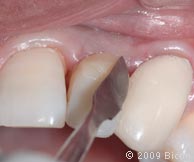

66. Вид интегрированной коронки (IAC).

67. Вид интегрированной коронки (IAC).

68. Вид спереди.